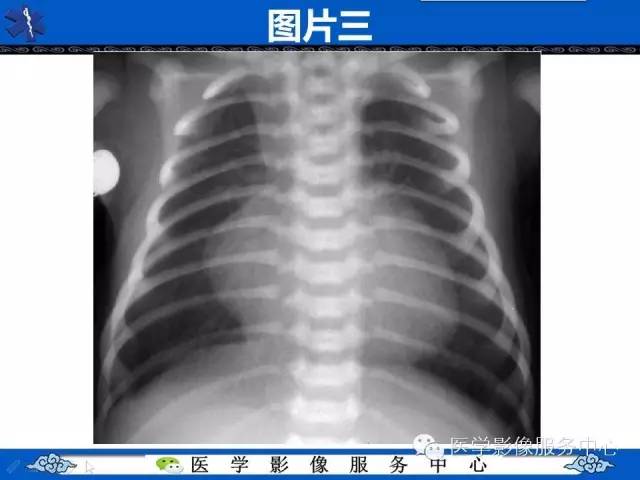

【影像征象】鸡蛋挂线征——大动脉转位征